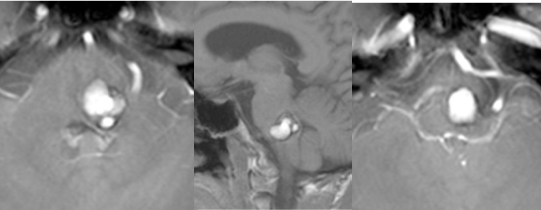

圖:術(shù)前顱腦MR影像顯示腦干腦橋占位,海綿狀血管瘤可能,出血活動(dòng)期